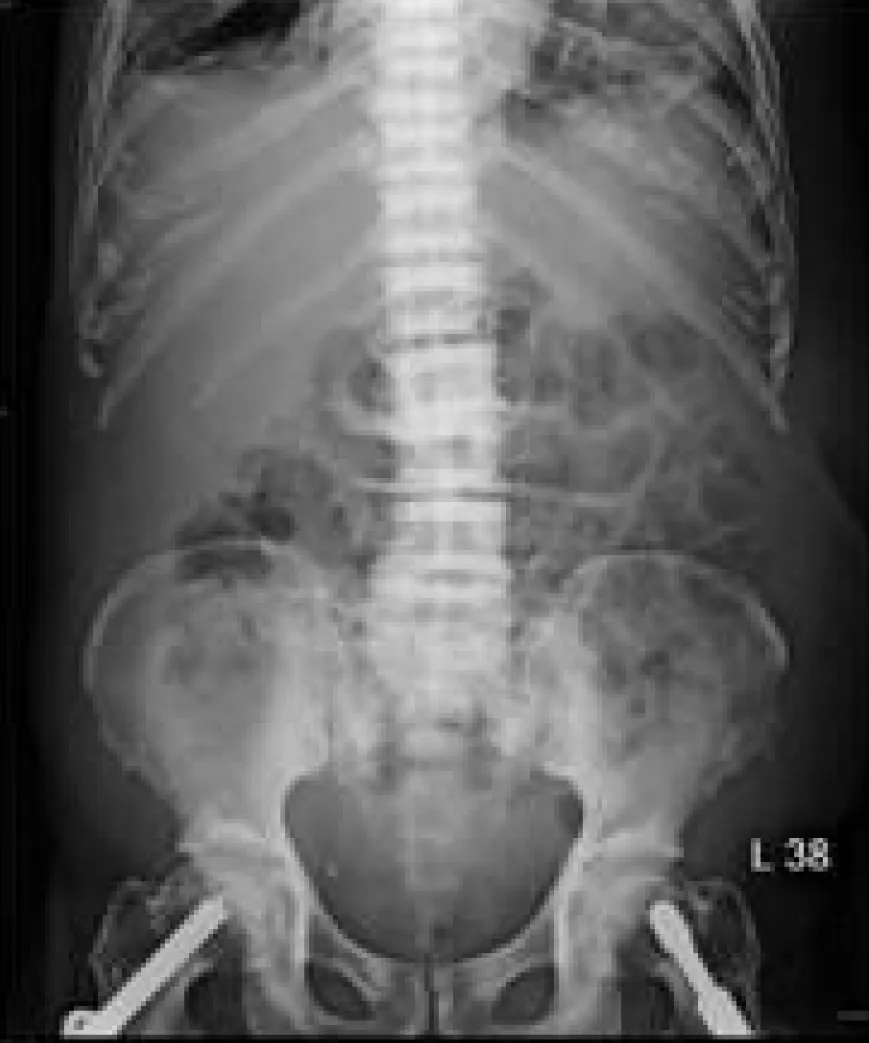

結合病患副甲狀腺素(PTH)上升的病史,這張腹部X光片中脊椎骨呈現典型的「橄欖球衣脊椎」(rugger jersey spine) 外觀,這是腎性骨病變 (renal osteodystrophy) 的經典表現。